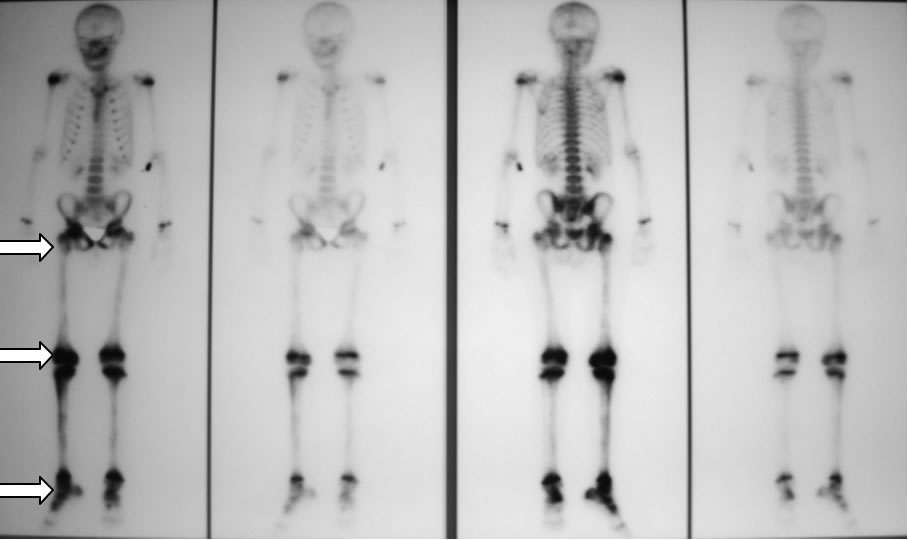

Quello che colpiva nella valutazione della diagnostica per immagini era l'aspetto, in corso di scinti- grafia, di ipercaptazione di tutto il femore, non solo delle articolazioni, dato che peraltro, vista la evidenza di artrite concomitante, non era stato particolarmente valorizzato pensando ad una generica “ipersensibilità” della scintigrafia. (figura 1)

Figura 1: riscontro di zone multiple di captazione (ginocchio, articolazione tibio-tarsica, femore destro e coxo-femorale destra).

Ripete una scintigrafia ossea nella ricerca di altre lesioni nel sospetto di una evoluzione in multifo-calità ma questa conferma solo l'ipercaptazione al femore di destra, negando la presenza di altre localizzazioni.